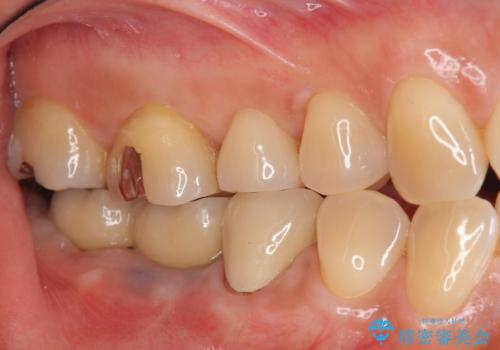

- 失った右下奥歯の機能回復を求めて来院されました。

取り外しの必要な入れ歯、もしくは手術の必要なインプラントのご提案を行い、しっかりと奥歯で物を噛みたいとの要望からインプラント治療を計画します。